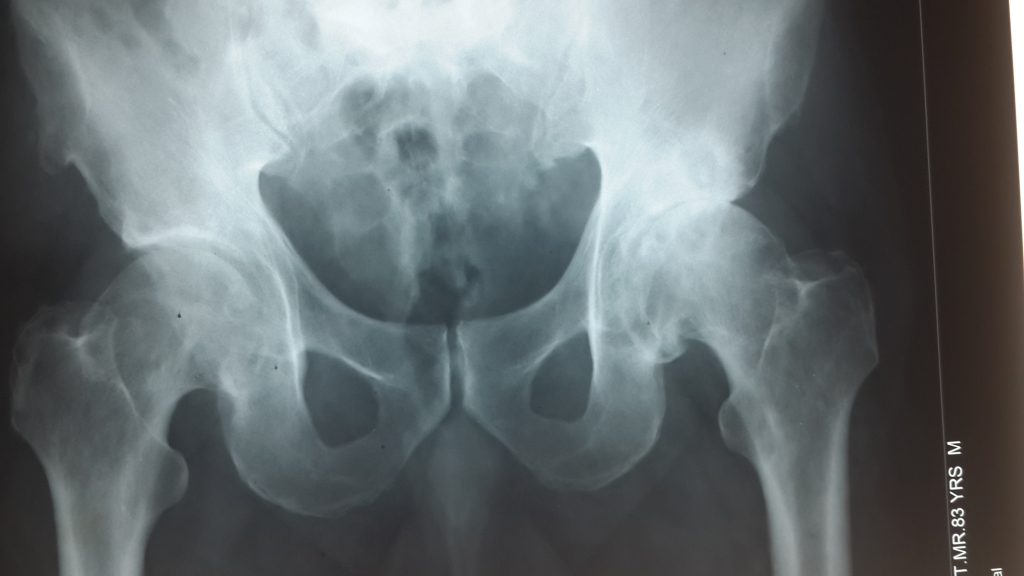

Osteoarthritis (oa) is the most prevalent type of arthritis, 1 with projections of 25% of the us adult population to be diagnosed by 2030. 2 symptomatic hip oa affects 8.7% of men and 9.3% of women over the age of 45 in the united states. Stem cell therapy for hips.

3 hip oa may result from cartilage loss, osteophyte formation, or changes in the shape of the femur head. How stem cell therapy works

What is regenerative medicine for hips? Mesenchymal stem cells have the potential to become many different types of cells, including chondrocytes (cartilage cells). Osteoarthritis (oe) avascular necrosis (avn) bursitis;

Hence, bmc seems to work in patients with mild to moderate hip arthritis, but not more severe hip arthritis. That is the main reason researchers are aggressively testing stem cells as a treatment for hip osteoarthritis. The stem cells are present in higher concentration in these procedures.